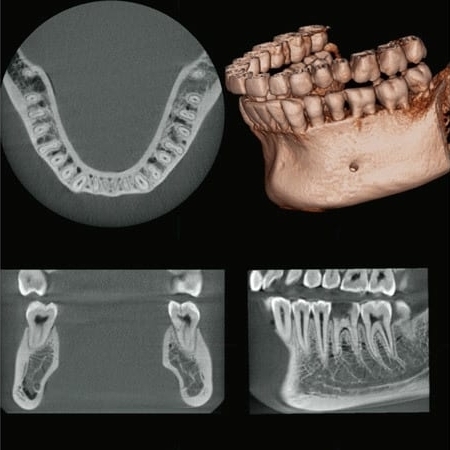

Information / DémonstrationPanoramique 3D & 2D

FOV Jusqu'à: Ø 150 X H 140

Ø 40 x H 40, Ø 40 x H 80

P ( M ) CHF 72'900.- H.T.* - Leasing CHF 1'181.- / 72 mois

Ø 40 x H 40, Ø 40 x H 80

Ø 80 x H 40, Ø 80 x H 50, Ø 80 x H 80

R 100 x H 40, R 100 x H 50, R 100 x H 80

P ( L ) CHF 79'900.- H.T.* - Leasing CHF 1'295.- / 60 mois

Ø 40 x H 40, Ø 40 x H 80

Ø 80 x H 40, Ø 80 x H 50, Ø 80 x H 80

R 100 x H 40, R 100 x H 50, R 100 x H 80

Ø 150 x H 50, Ø 150 x H 75, Ø 150 x H 140